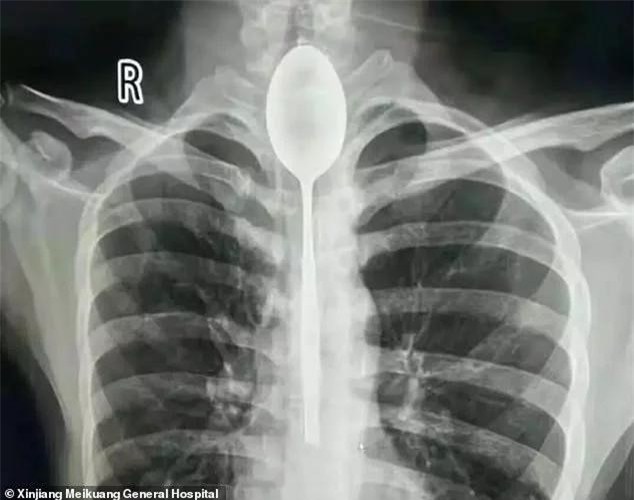

Một người đàn ông ở khu tự trị Tân Cương nuốt chiếc thìa dài đến 20cm vào người trong một vụ cá cược nhưng không chịu đến bác sĩ vì thấy vẫn ăn uống được bình thường suốt một năm qua.